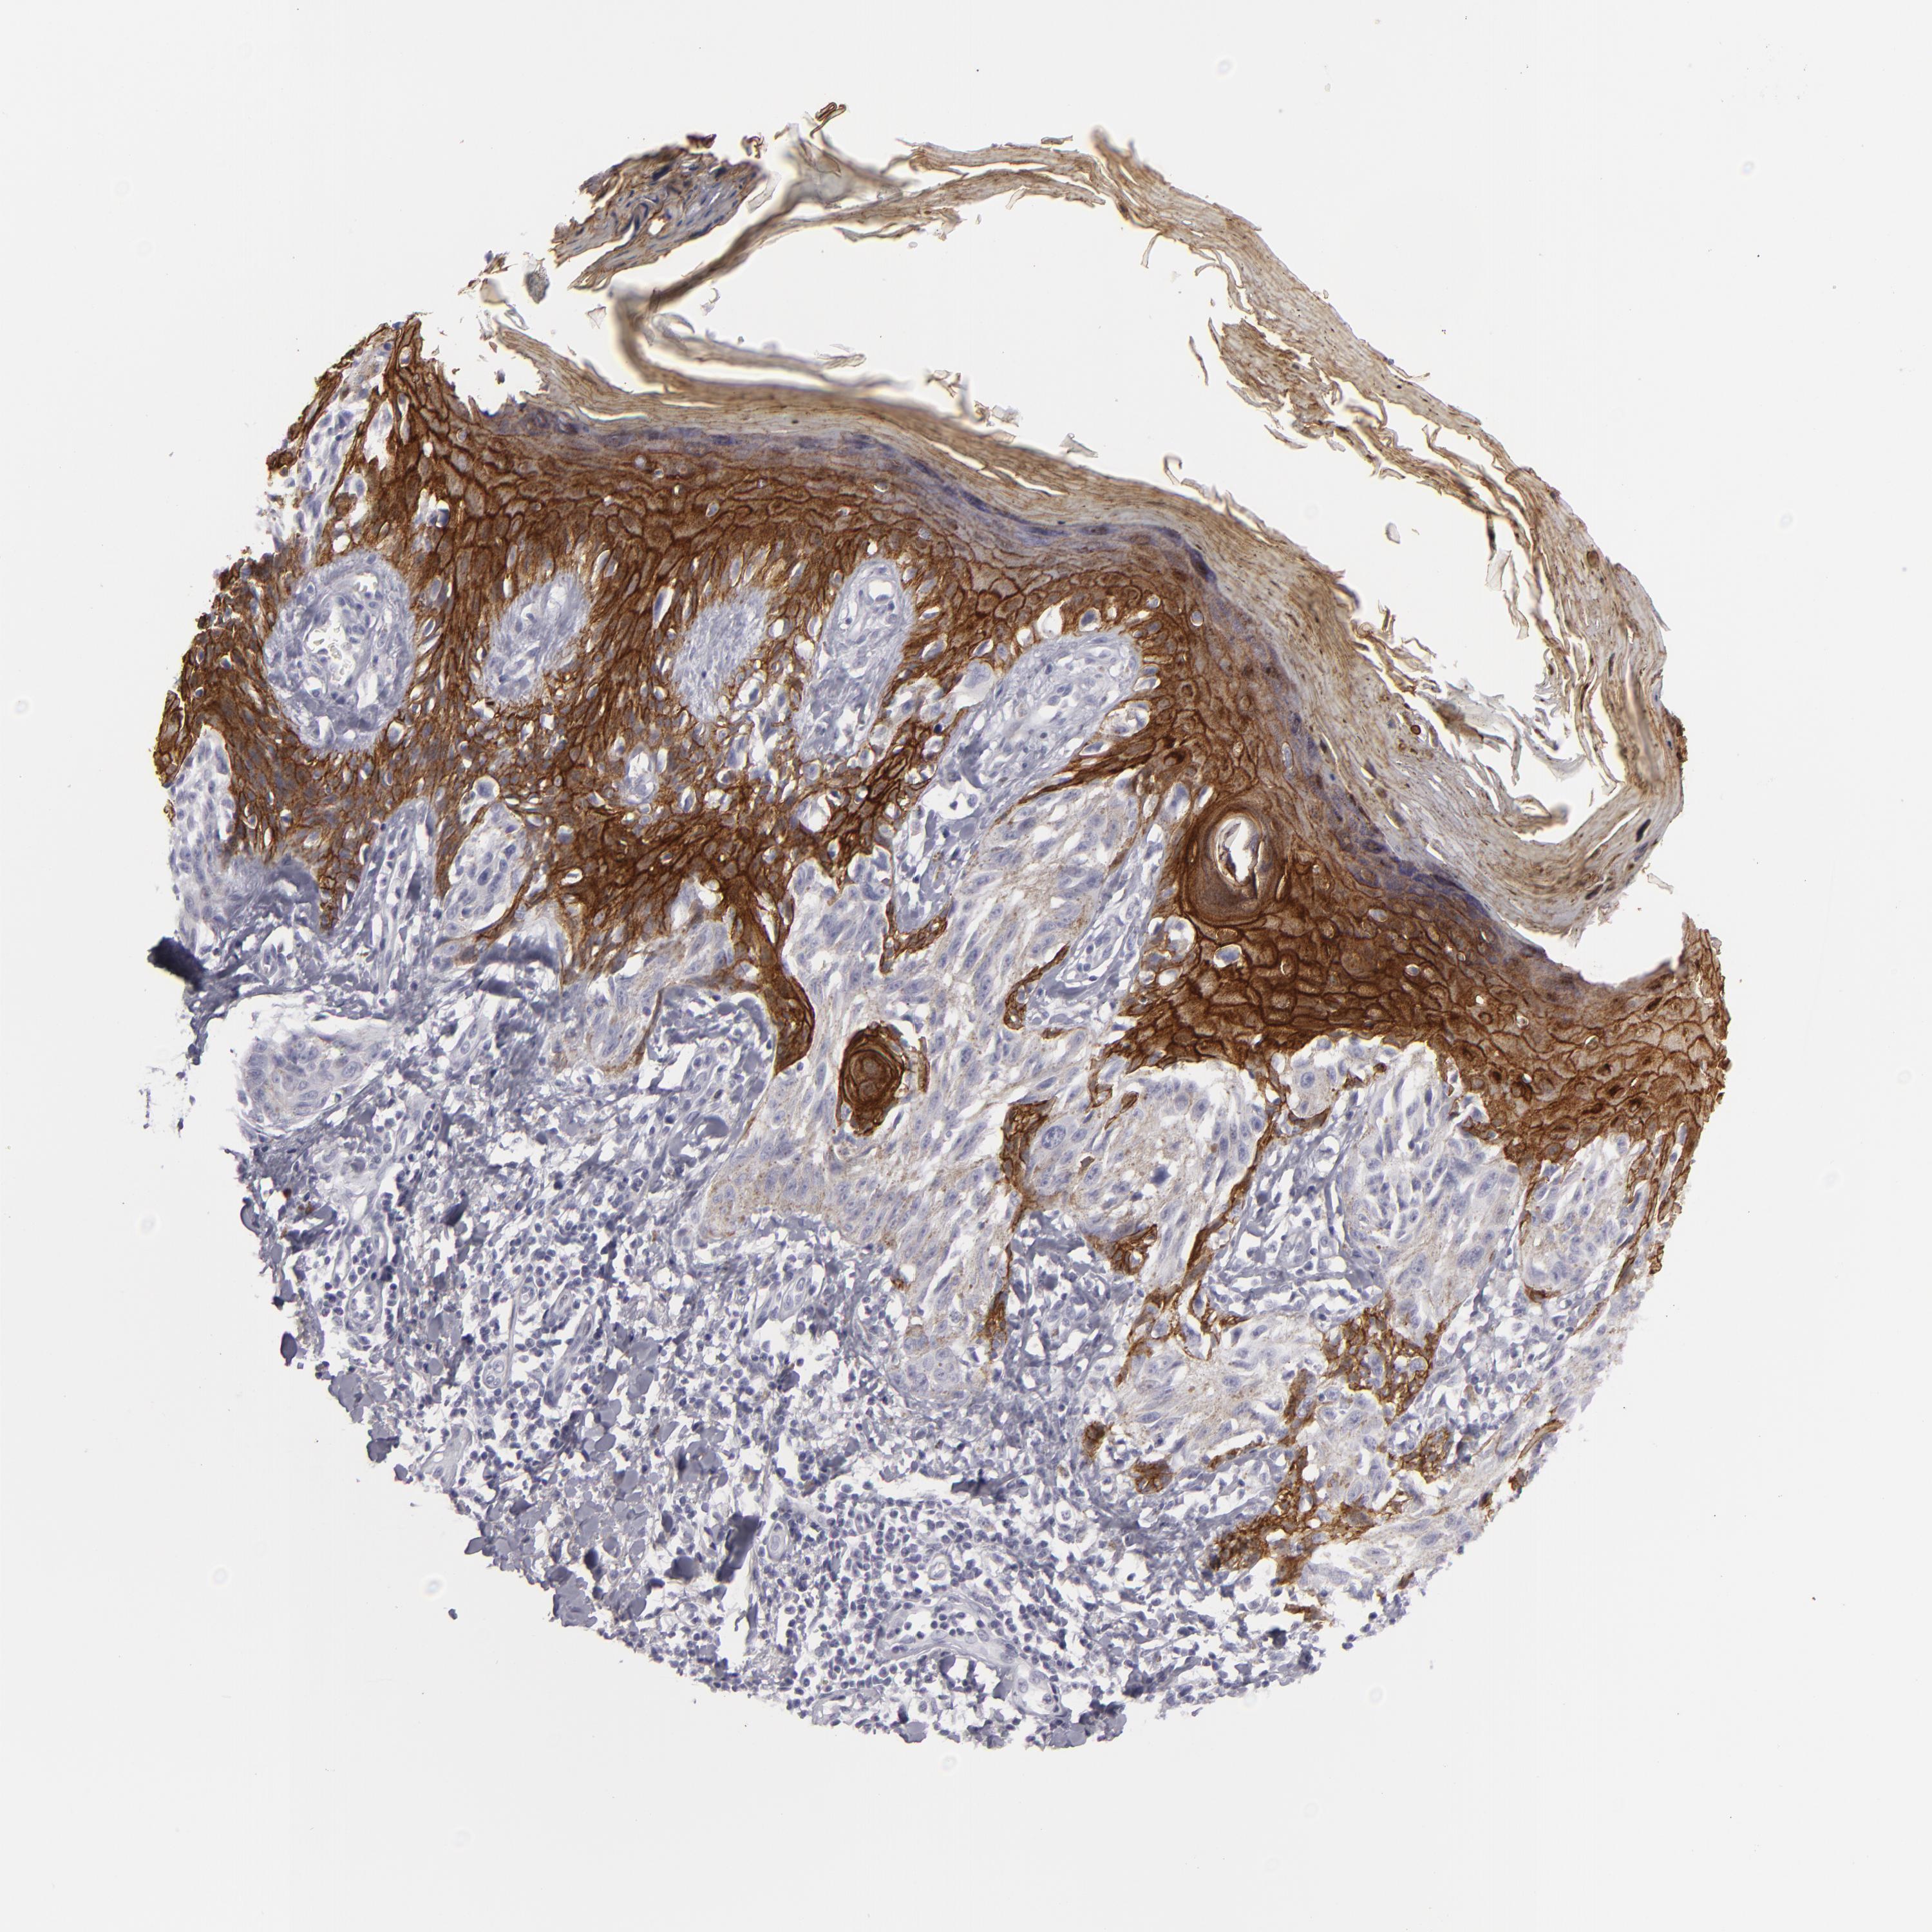

MELANOMA - Protein expressioni

A mouse-over function shows sample information and annotation data. Click on an image to view it in a full screen mode. Samples can be filtered based on level of antibody staining by selecting one or several of the following categories: high, medium, low and not detected. The assay and annotation is described here.

Note that samples used for immunohistochemistry by the Human Protein Atlas do not correspond to samples in the TCGA dataset.

Antibody stainingi

Antibody staining in the annotated cell types in the current human tissue is reported as not detected, low, medium, or high, based on conventional immunohistochemistry profiling in selected tissues. This score is based on the combination of the staining intensity and fraction of stained cells.

Each image is clickable and will lead to virtual microscopy that enables deeper exploration of all samples and also displays staining intensity scores, fraction scores and subcellular localization as well as patient and tissue information for each sample.

Antibody HPA032047

Antibody CAB002139

Staining

High

Medium

Low

Not detected

Intensity

Strong

Moderate

Weak

Negative

Quantity

>75%

75%-25%

<25%

None

Location

Nuclear

Cytoplasmic/membranous

Cytoplasmic/membranous,nuclear

Malignant melanoma, NOS

Malignant melanoma, Metastatic site